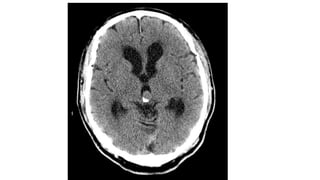

PINEAL CYST • Theyare common, usually asymptomatic, and typically found incidentally. • Common in women. • The cyst typically contains proteinaceous fluid that, as a result, does not follow CSF on imaging. • Internal haemorrhage may also be present

• 39.

CT Findings • Pinealcysts appear as well circumscribed fluid density lesions. • A thin rim calcification is seen in ~25%. • Thin, smooth peripheral enhancement is also often seen. • The internal cerebral veins are elevated and splayed by the cyst.

• #42 CT of the brain demonstrates no focal mass or abnormality. Incidental note is made of a 20 mm pineal cyst.

• #43 Incidentally well-circumscribed fluid density lesion with rim calcification is seen at pineal topography with no contrast enhancement.